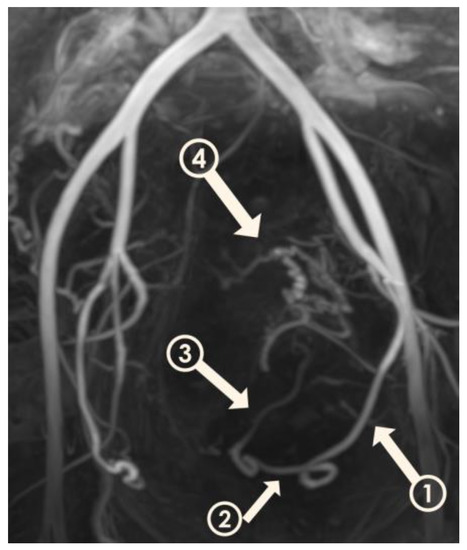

2.4. Visual Classification of Uterine Arteries

Visualization of UAs was scored by two radiologists in consensus at four time points: before UAE, at 3 months after UAE, at 6 months after UAE, and at 12 months after UAE. A 4-point scale (Figure 2) was established for classifying the degree of visualization of the right and left UAs individually: 1, visualization until the descending segment; 2, visualization until the transverse segment; 3, visualization until the ascending segment; and 4, visualization until the peritumoral plexus. By assessing the variation in scores at these four time points, we were able to estimate the occurrence of recanalization in our patients (Figure 3A–D). We used this information to divide patients into two groups: those in whom scores for both right and left UAs remained the same or decreased over time (Group 1) (Figure 4A–D), and patients whose scores increased (Group 2), suggesting luminal recanalization. If either of the UAs had an increase in score, the patient was classified as Group 2.

Figure 2.

Three-dimensional non-contrast-enhanced magnetic resonance angiography image from a 49-year-old woman. The model is rotated to show the left uterine artery and its segments. Descending segment (arrow 1); transverse segment (arrow 2); ascending segment (arrow 3); peritumoral plexus (arrow 4).